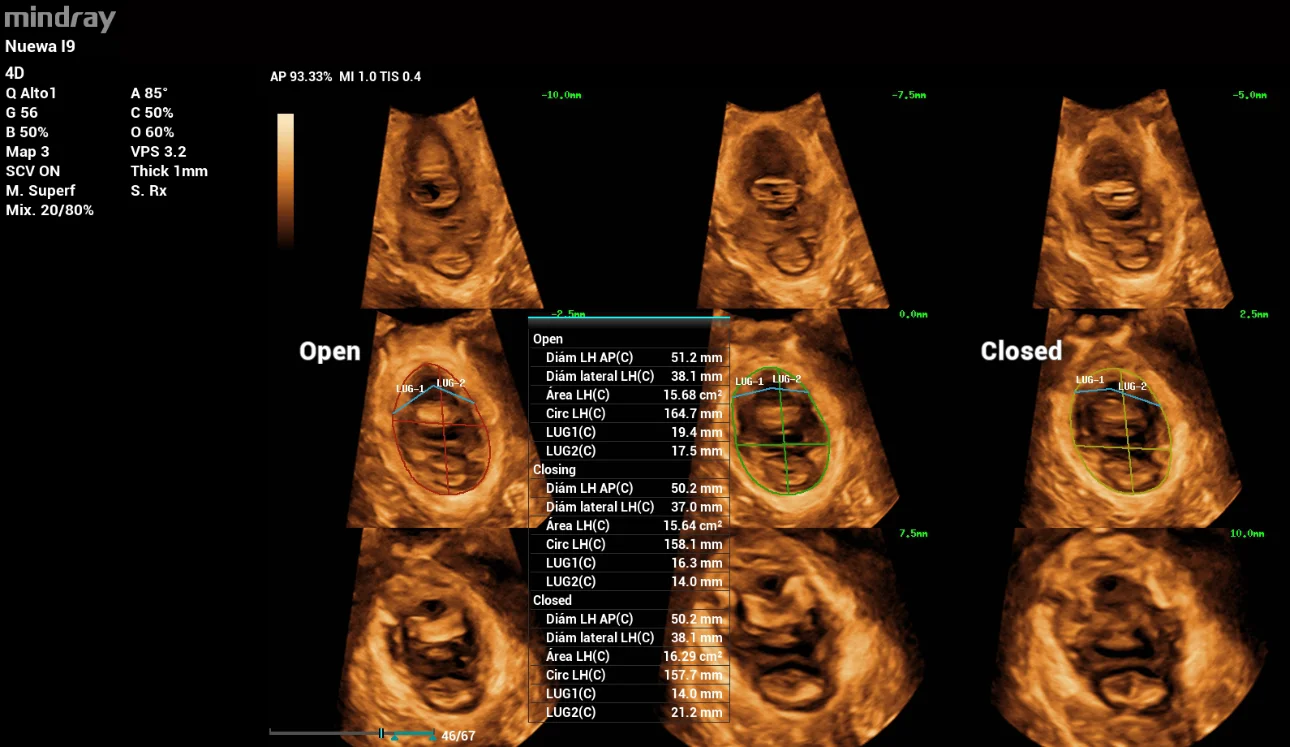

In the 3D/4D exploration mode, the Levator ani muscle was observed intact. In the tomographic or multi-slice ultrasound evaluation (iPage) during contraction, the following measurements were obtained: left GAP 24mm, right GAP 25mm (Figure 9. a). The area of the Levator hiatus during Valsalva was 30cm2 with moderate ballooning (Figure 9. b).

pelvic-floor-ultrasound-stress-incontinence-fig9

Figure 9: Levator ani muscle evaluation: 3. a during Contraction, 3. b during Valsalva